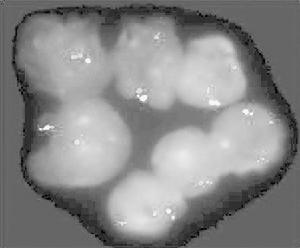

2.骨髓 粒系增生,可見病態造血紅系病態造血少見,巨核細胞減少,單核系占5%~10%。骨髓病理在部分患兒可見纖維增生,但較Ph1CML少見。